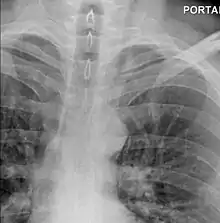

The diagnosis of Boerhaave's syndrome is suggested on the plain chest radiography and confirmed by chest CT scan. The initial plain chest radiograph is almost always abnormal in patients with Boerhaave's syndrome and usually reveals mediastinal or free peritoneal air as the initial radiologic manifestation. With cervical esophageal perforations, plain films of the neck show air in the soft tissues of the prevertebral space.

Hours to days later, pleural effusion(s) with or without pneumothorax, widened mediastinum, and subcutaneous emphysema is typically seen. CT scan may show esophageal wall edema and thickening, extraesophageal air, periesophageal fluid with or without gas bubbles, mediastinal widening, and air and fluid in the pleural spaces, retroperitoneum or lesser sac.